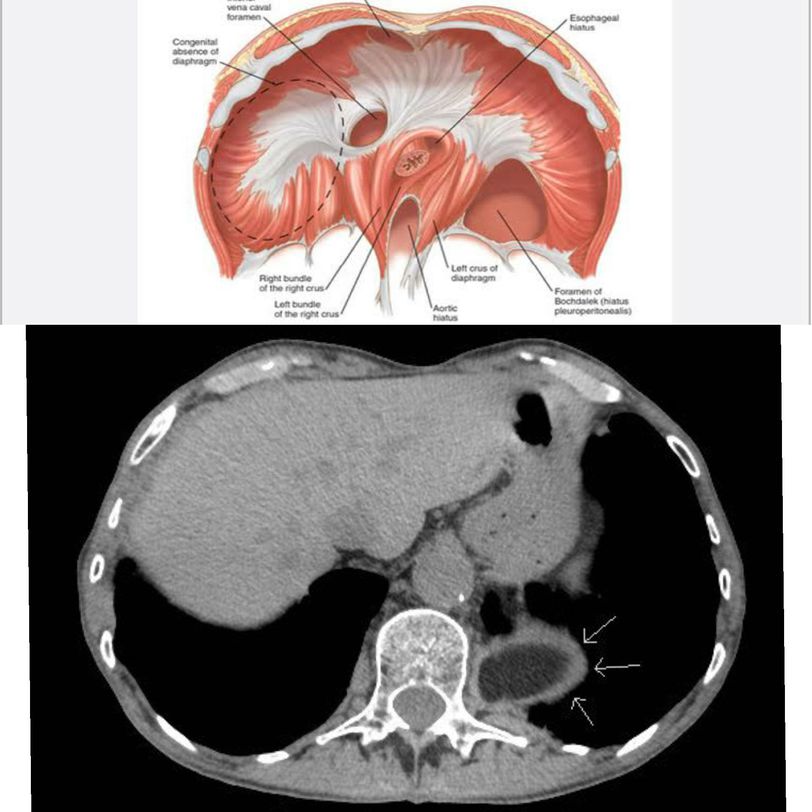

A Bochdalek hernia is one of the types of congenital diaphragmatic hernias. Diaphragm develops from 4 components including septum transversum ( central tendon), dorsal mesentery of esophagus (crura of diaphragm), pleuroperitoneal membranes and muscular ingrowth from lateral body walls. Bochdalek hernia is an opening in the posterolateral region of diaphragm due to defective formation and/or fusion of the pleuroperitoneal membranes with the other three parts of the diaphragm. This results in continuity between the pleural and peritoneal cavities. This condition is more common on the left side. If the normal fusion of pleuroperitoneal membranes is impaired during the period when intestines return to the abdomen from the umbilical cord i.e in 10th week of gestation, some viscera may pass into the thorax. This abdominal viscera compresses the heart and lungs. Mortality in these cases results not from the hernia or viscera but due to the hypoplastic lungs which were compressed during their period of development. Such cases are associated with pulmonary hypertension due to decreased vascular cross sectional area. Hypoxia can further cause pulmonary vasoconstriction which may be reversed by inhalation of nitric oxide. Lungs can achieve their normal size after repositioning the abdominal viscera and reparing the diaphragmatic defect. The axial CT of the lung bases shows herniation of abdominal fat contents into the lower posterior left hemithorax through the left hemidiaphragm (arrows). Image via: https://images.app.goo.gl/cm4uH57FK9qNUHi27 https://radiologypics.com/2013/02/05/bochdalek-hernia/amp/